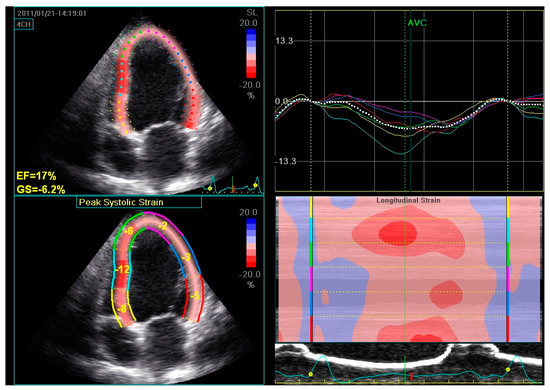

2.1. Assessment of LV Function and Dyssynchrony

4.1. Assessment of LV Remodelling

- Delgado, V.; Ypenburg, C.; van Bommel, R.J.; Tops, L.F.; Mollema, S.A.; Marsan, N.A.; Bleeker, G.B.; Schalij, M.J.; Bax, J.J. Assessment of left ventricular dyssynchrony by speckle tracking strain imaging comparison between longitudinal, circumferential, and radial strain in cardiac resynchronization therapy. J. Am. Coll. Cardiol. 2008, 51, 1944–1952. [Google Scholar] [CrossRef]

- Valzania, C.; Gadler, F.; Boriani, G.; Eriksson, M.J. Changes in global longitudinal strain during rest and exercise in patients treated with cardiac resynchronization therapy. Clin. Physiol. Funct. Imaging 2012, 32, 310–316. [Google Scholar] [CrossRef] [PubMed]